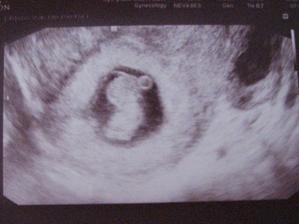

Od ledna 2009 jsem dochazela 1x mesicne na kontroly k Dr., protoze jsem mela cystu na vajecniku, tak ji hlidal a uz to vypadalo, ze po prazdninach nastoupim na operaci, kdyz mi v cervnu na kontrole Dr. rekl, ze jsem tehotna. Byl to sok. Endometrioza a cysta a povedlo se! A to nam na zacatku naseho snazeni doktor pres IVF prorokoval nulovou sanci na prirozene poceti. Jsme dukaz, ze i zazraky se deji. Ted si jen prejeme, aby vse dobre dopadlo a mimco bylo zdravy.

Velky UTZ 26.9.2009 - Byli jsme uplne nadseni, miminko je zdrave, dostali jsme fotku a video a take vime pohlavi, ale nerekneme